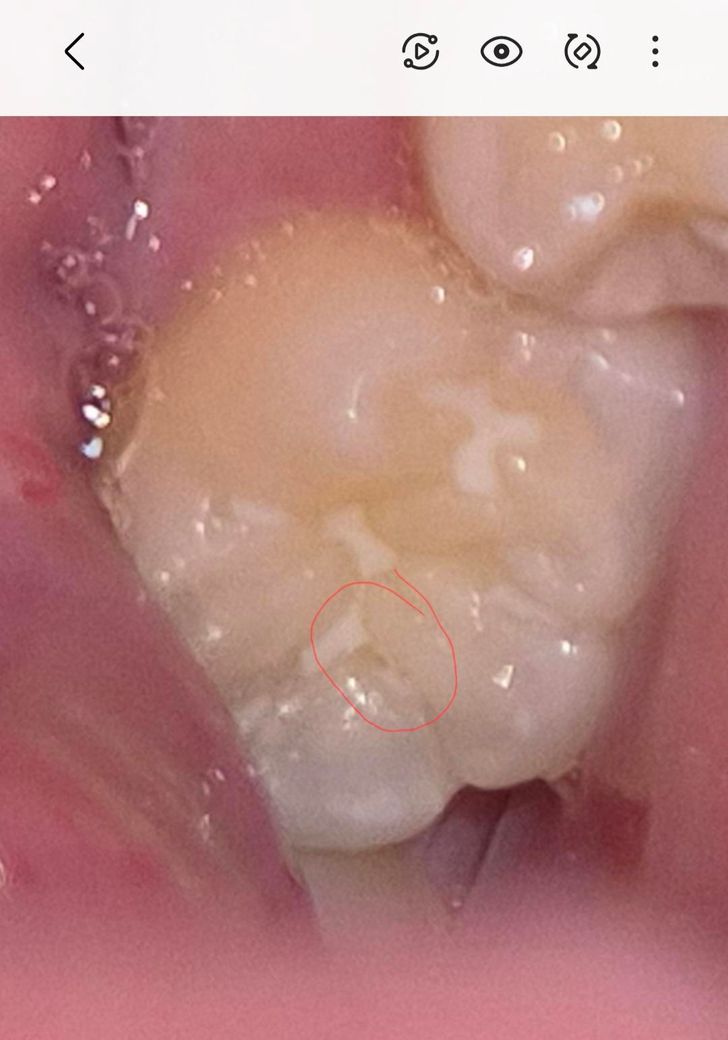

아이 어금니 실란트 떨어진 부위? 충치인건지요

어금니 동그라미친 부분인데요 , 실란트가 부분부분 삭제되긴했어요 근데 유독 저부분만 뒤쪽이긴하지만 각도때문인건지 신경쓰여서요 치과에서는 충치는아니고 실란트가 떨어져서 그렇고 빛에따라서 음영? 암튼 눈으로보면 뭐가껴있거나 그런식으로 색이 보여질수는있다고, 치과빛으로비춰 거울로보고 검진해도 충치는아니라고하셨는데 .. 왤케신경이 쓰이는건지.. 제가 어떤각도에서보면 유독저부분이 진짜뭐가껴있거나 충치같은색으로 보이기도하고 또어떤각도에선 괜차나보이기도하고 그러긴해요 ㅜㅜ 다른전문가분들의 의견이궁금합니다

충치는 아닌거 같고 저 사이에 음식물이 꼇거나 어둡게 보여서 그러는거 같으니 걱정하지 않으셔도 될것같습니다.

충치는 아니고 골짜기의 그림자 같습니다 다만 저렇게 실란트가 떨어지고 틈이 있는채로 두면 충치가 잘생깁니다 보완을 해주면 좋을 것 같습니다